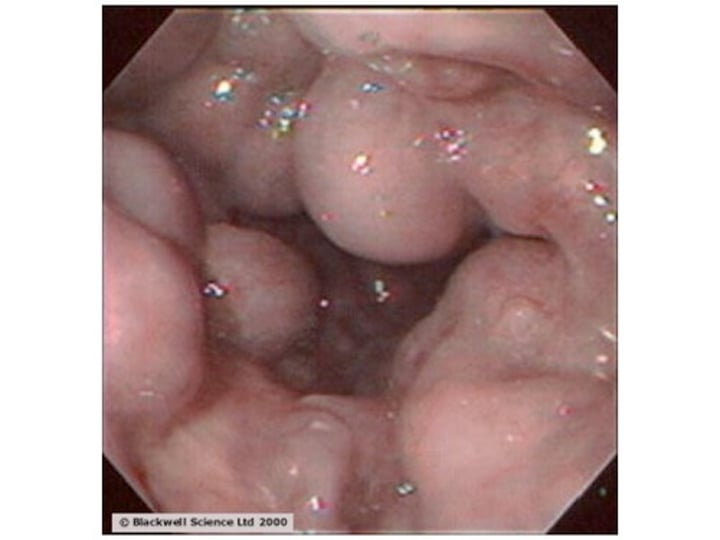

What is a colonoscopy?

Visualization of colon using a flexible scope.